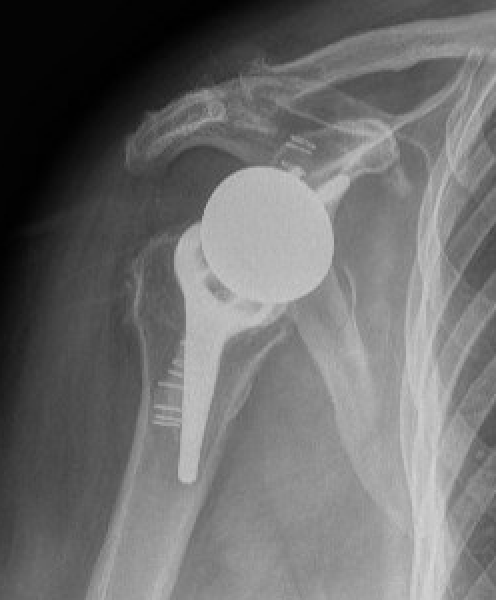

Chronic locked with large Hill Sachs treated with rTSA + glenoid bone graft

Chronic locked with large Hill Sachs and normal glenoid treated with rTSA + glenoid bone graft